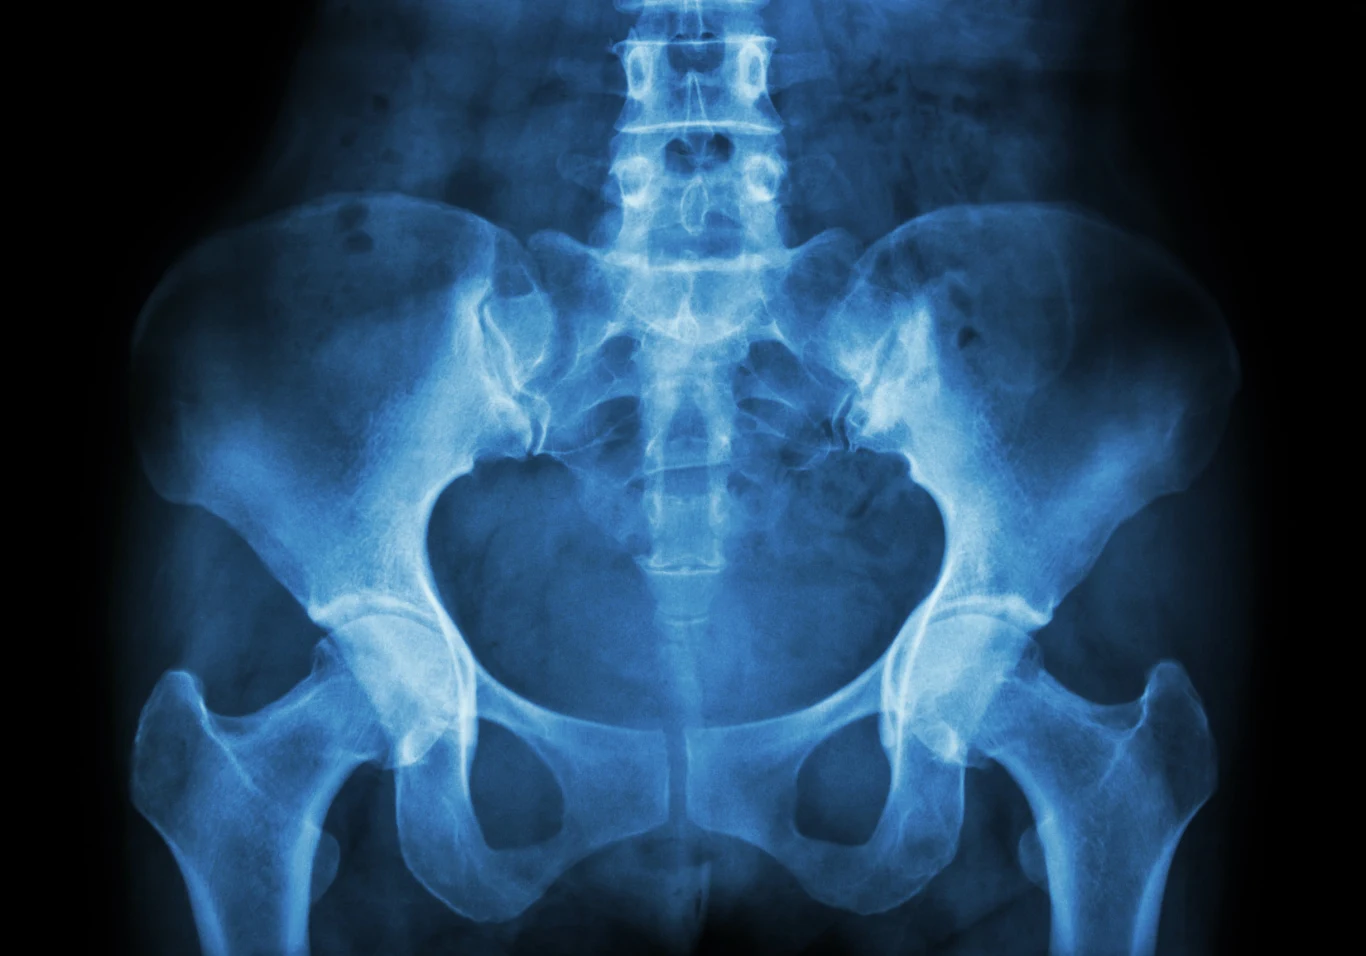

Pewne jest, że utrata ogona miała głęboki wpływ na ewolucję reszty naszego ciała i ukształtowała człowieka może bardziej, niż jakakolwiek inna zmiana. Mięśnie, które u naszych przodków odpowiadały za poruszanie ogonem, przekształciły się w rodzaj siatki na miednicy. Ten mięśniowy hamak stanowi podstawę, która utrzymuje ciężar organów u istot poruszających się w pozycji wyprostowanej. Bez tego najprawdopodobniej nasi przodkowie nigdy nie nauczyliby się pokonywać długich dystansów na dwóch nogach.